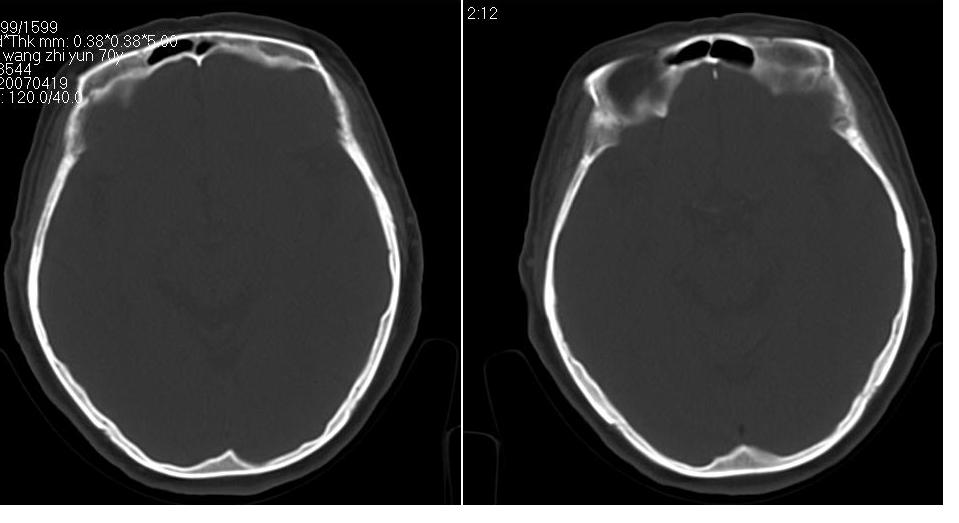

女 70岁,左侧上颌窦腔内肿物。

窦壁骨质增厚,密度增高,考虑慢性炎症,息肉样变。

左侧颌窦内可见高密度影充填,窦壁增厚 考虑 左颌窦囊肿 慢性炎症

左侧上颌窦内软组织影,略呈膨胀性,窦壁骨质增生硬化,考虑为黏膜下囊肿.左侧筛窦炎

左侧上颌窦内软组织密度影,窦壁骨质增厚,密度增高,窦口扩大,考虑左侧上颌窦慢性炎症,息肉样变。